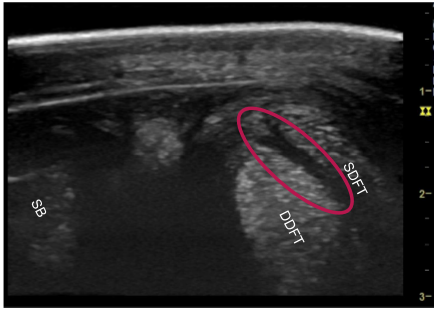

• which structure is injured?

manica flexoria due to the fluid between the DDFT and SDFT